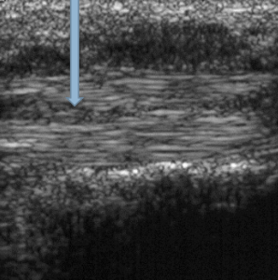

What does the arrow indicate? | A cleft (tear) in the tendon |